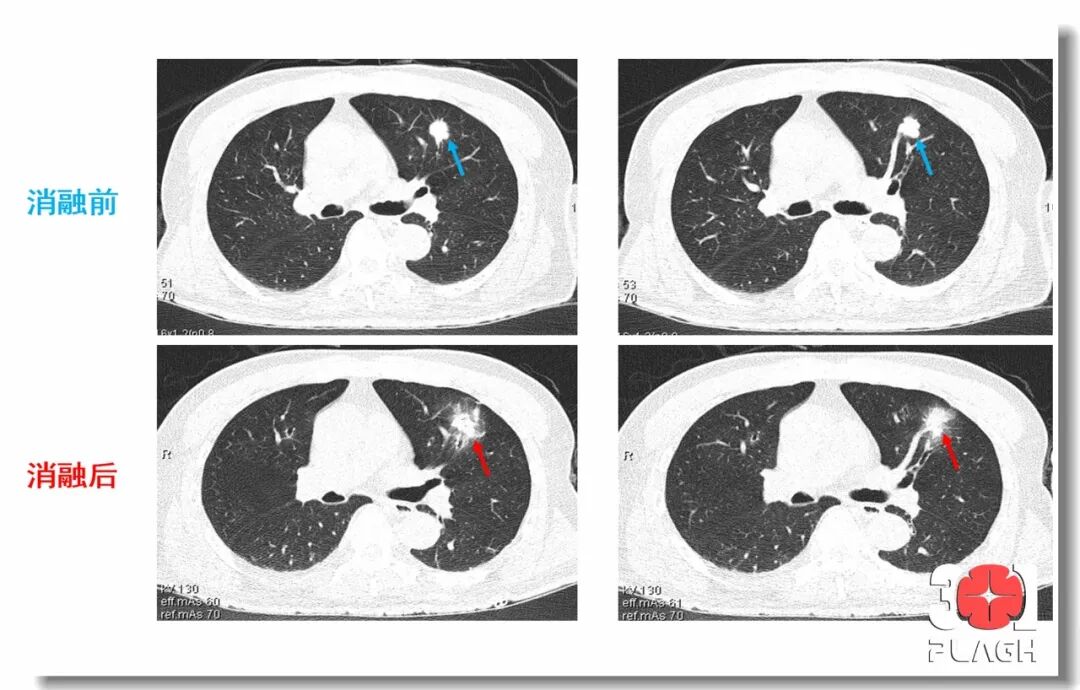

图片

▲消融前后即时肺部病变对比